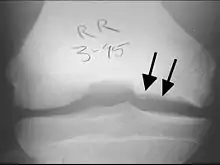

X-rays show lucency of the ossification front in juveniles. In older people, the lesion typically appears as an area of osteosclerotic bone with a radiolucent line between the osteochondral defect and the epiphysis. The visibility of the lesion depends on its location and on the amount of knee flexion used. Harding described the lateral X-ray as a method to identify the site of an OCD lesion.[36]

Sagittal MRI: Linear low T1 signal at the articular surfaces of the lateral aspects of the medial condyle of the femur confirms the presence of OCD.